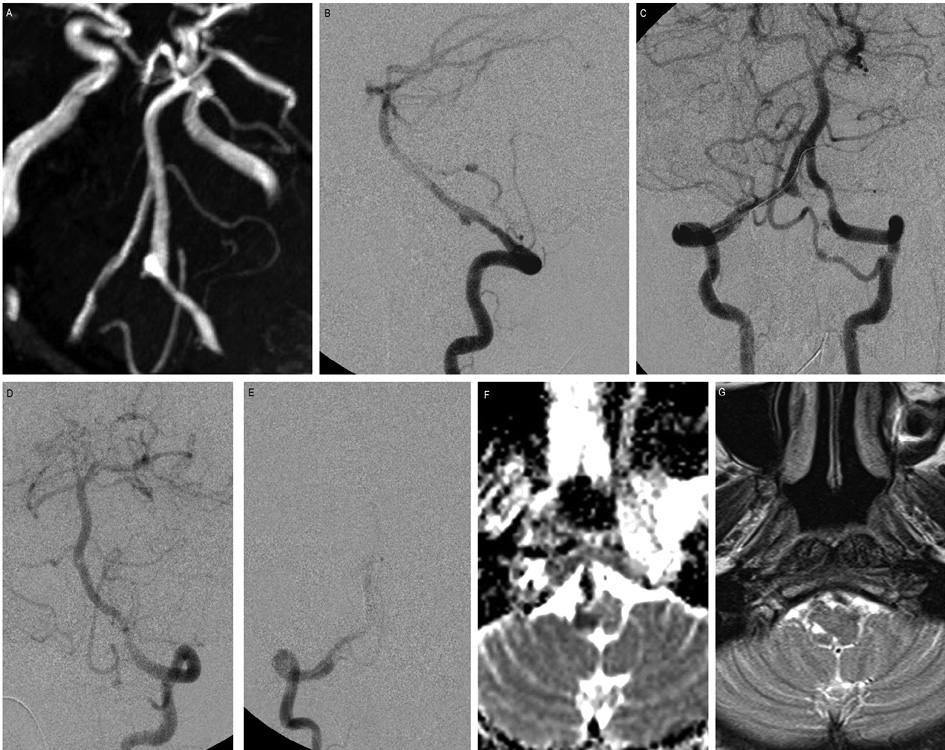

We performed PAO of the VA dissecting aneurysm in one patient (Figure 2). In post-procedure, there was complete occlusion of the parent artery without filling of the aneurysm. However, the patient developed acute vertigo and dysarthria during the first 24 hours after the procedure. The MRI showed a small acute infarct in the right inferior cerebellar peduncle. The patient was then treated conservatively with corticosteroids and heparinization followed by oral aspirin. The mean blood pressure was kept on the higher side (mean BP= 100 mm Hg). The patient completely recovered on follow-up. As it was reported, insufficient crossflow or thrombo-embolic phenomenon from the occlusion site may lead to late-onset ischemic events [37], so we can presume a transient thrombo-embolic episode in a small perforating artery for such presentation in our case.

Figure 2. PAO of vertebral artery dissecting aneurysm.

45 years old female presented with headache and SAH. (A) TOF MR angiogram flipped image shows a gradual narrowing of the right V4 vertebral artery with a fusiform dilatation. (B) The lateral projection of the right vertebral artery angiogram reveals a dissecting aneurysm arising from the V4 segment. (C) Bilateral vertebral artery angiogram, with the microcatheter placed for PAO. The left PICA was supplying the right PICA territory. (D and E) Post-coiling check– left VA angiogram shows complete obliteration of the aneurysm. In the immediate post-procedural period, the patient developed vertigo and dysarthria. (F)MRI performed 2 days after the procedure, DWI showed a small infarct at the right inferior cerebellar peduncle. (G) Follow-up MRI T2WI showed a small area of gliosis in the same area. The patient had full recovery during her hospital stay and was discharged with no neurological deficits.